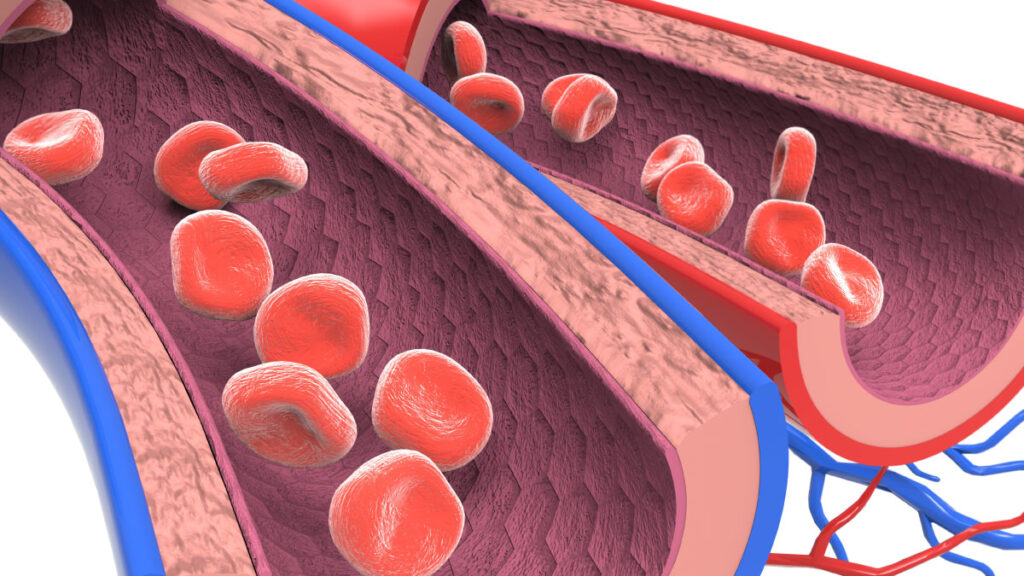

Una característica muy importante del aparato vascular es que todos los vasos sanguíneos son distensibles.

La naturaleza distensible de las arterias las permite acomodarse al gasto pulsátil del corazón y superar las pulsaciones de la presión. Esta capacidad proporciona un flujo de sangre continuo y homogéneo a través de los vasos sanguíneos muy pequeños de los tejidos.

Los vasos más distensibles del cuerpo son las venas, capaces de almacenar 0,5-1 litros de sangre extra; las venas ejercen de reservorio para almacenar grandes cantidades de sangre extra que puede utilizarse siempre que se requiera en cualquier otro punto de la circulación.

Las paredes de las arterias son más gruesas y bastante más fuertes que las de las venas, por lo que, como media, las venas son unas ocho veces más distensibles que las arterias.